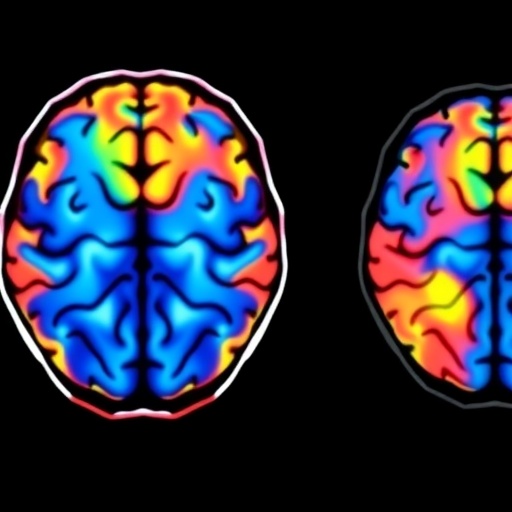

Brain Maintenance Biomarkers in Aging and Neurodegeneration

Brain Imaging Study Reveals Ethnoracial Variations in Dementia Risk and Progression